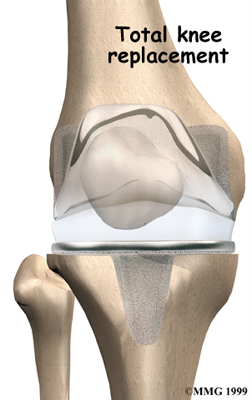

Artificial Knee Replacement

An artificial knee replacement is the ultimate solution for advanced knee OA.

Surgeons prefer not to put a new knee joint in patients younger than 60. This is because younger patients are generally more active and might put too much stress on the joint, causing it to loosen or even crack. A revision surgery to replace a damaged prosthesis is harder to do, has more possible complications, and is usually less successful than a first-time joint replacement surgery.

Related Document: FYZICAL Therapy - Florence's Guide to Artificial Joint Replacement of the Knee